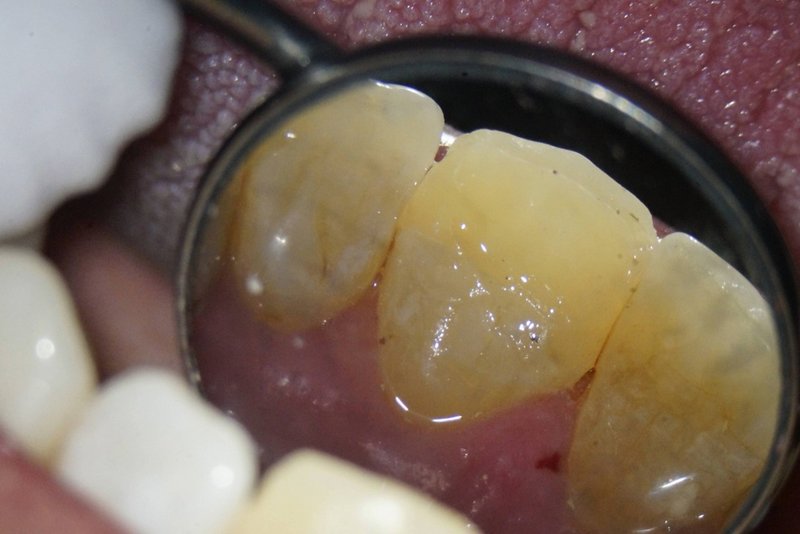

Kronenfraktur: Zustand vor der Wurzelkanalbehandlung